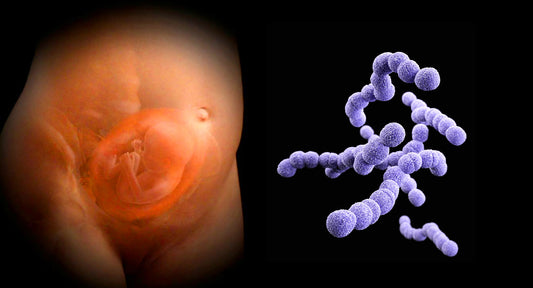

Group B strep